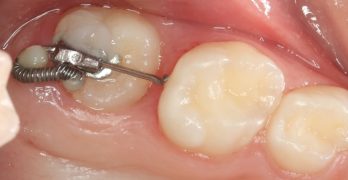

BDR CCCIV: Intrusión de un molar por medio de mini-tornillo para prótesis.

Ya es viernes, y el Baúl del Recuerdo lo sabe. Hoy traemos una nota llamada Intrusión de un molar sobreerupcionado por … [Leer más...] acerca de BDR CCCIV: Intrusión de un molar por medio de mini-tornillo para prótesis.